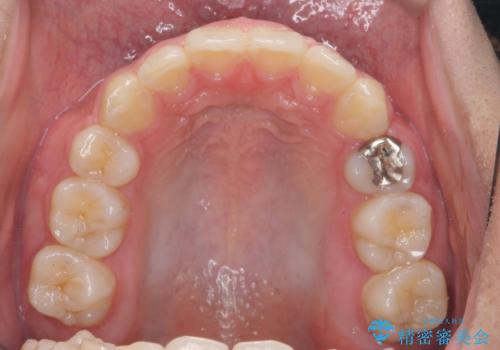

- 前歯のがたつきが原因で歯ブラシしづらい、見た目を改善したい!と矯正治療を希望され来院されました。

スペースの不足が見られるため、小臼歯の4本抜歯を行いマルチブラケットを用いた矯正治療を計画します。